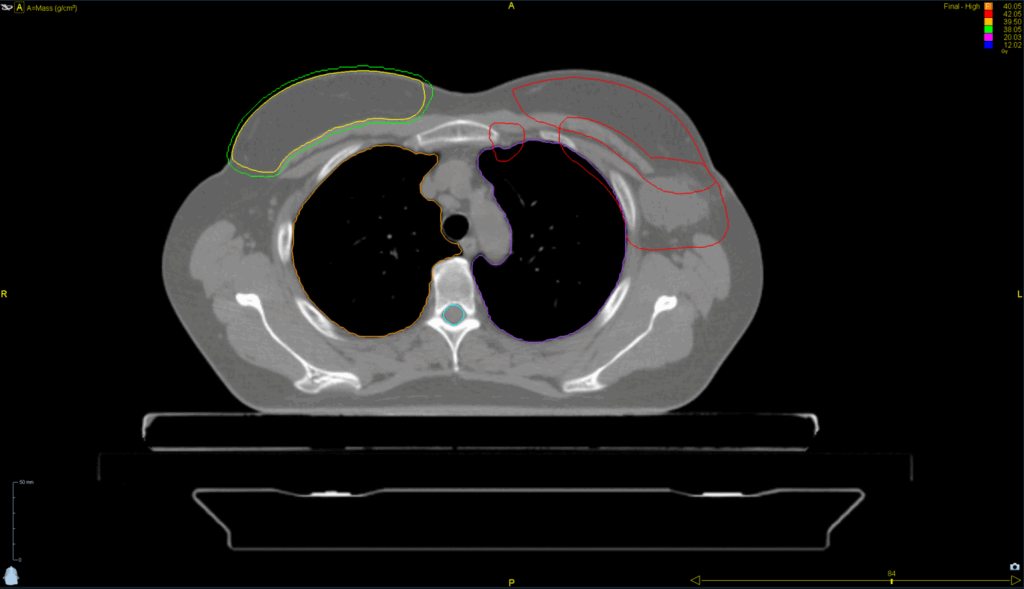

Planning CT Images

Treatment Plan Images